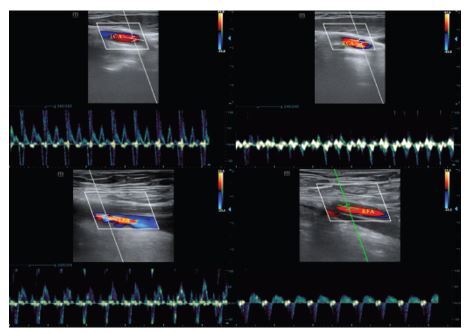

Methods: For this prospective study we enrolled 31 cardiac arrest (CA) patients who presented to the emergency department (ED) and 13 healthy volunteers as point-of-care ultrasound (POCUS) controls. Two physicians not involved in the resuscitation team performed POCUS of the bilateral carotid and femoral arteries during chest compression within the first 10 minutes of CPR. The clinical data and presumed CA cause were recorded. We observed the arterial pulse and measured the peak systolic velocity (PSV). The EtCO2 values during POCUS were also recorded. We explored the correlation between arterial PSV and EtCO2.

Results: The mean age of the patients was 69 ± 2 years, and 22 were male. Of 25 patients who experienced out-of-hospital cardiac arrest, 18 had an average no/low-flow time >30 minutes before ED arrival. Five patients achieved return of spontaneous circulation (ROSC). We found no significant difference in arterial PSV between ROSC and non-ROSC patients. The PSV of the left femoral artery was most consistently and positively correlated with EtCO2 in CA patients (R2 0.35, P=0.003).

Conclusion: Detection of arterial peak systolic velocity by point-of-care ultrasound, especially of the left femoral artery, might be a feasible method for non-invasive, real-time monitoring of chest compression effectiveness during CPR.